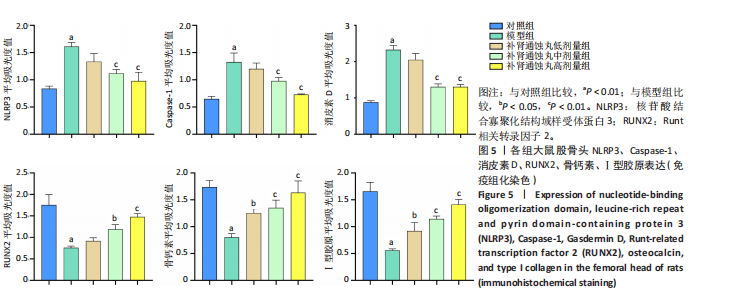

.1 实验动物数量分析 参加实验SD大鼠数量为50只,均进入结果分析。 2.2 Micro-CT检测结果 通过Micro-CT观察各组大鼠股骨头区域骨质变化,见图1。乙醇会导致大鼠股骨头软骨下骨骨量明显减少,骨小梁排列出现紊乱、稀疏等状况,而补肾通蚀丸能够改善上述情况,且呈现一定的剂量效应。模型组骨小梁厚度、骨小梁数目、骨体积分数、骨密度较对照组显著降低(P < 0.01),模型组骨小梁间隙较对照组则显著升高(P < 0.01)。经过不同剂量补肾通蚀丸干预后,各项指标均出现不同程度的逆向改变;其中,与模型组比较,补肾通蚀丸高剂量组骨小梁厚度、骨小梁数目、骨体积分数、骨密度均显著升高(P < 0.05),骨小梁间隙则显著降低(P < 0.05);与模型组比较,补肾通蚀丸中剂量组骨体积分数、骨密度显著升高(P < 0.05),骨小梁间隙则显著降低(P < 0.05);而补肾通蚀丸低剂量组仅在骨小梁间隙指标上较模型组显著降低(P < 0.05),见图2。 2.3 苏木精-伊红染色结果 与对照组比较,模型组大鼠股骨头出现核固缩现象,多见脂肪空泡,部分骨小梁出现断裂、变细;补肾通蚀丸低、中、高剂量组骨细胞核固缩和脂肪空泡较模型组有所减少;在整体结构方面,补肾通蚀丸低剂量组骨小梁变细现象较模型组未见明显改善,但断裂情况有所改善;而补肾通蚀丸中、高剂量组骨小梁断裂、变细情况较模型组均明显改善,见图3;在空骨陷窝率方面,模型组较对照组显著增高(P < 0.01);补肾通蚀丸中、高剂量组较模型组有所降低(P < 0.05),见图3。 2.4 免疫组化染色结果 与对照组比较,模型组NLRP3、Caspase-1、消皮素D蛋白表达明显增强,而Runt相关转录因子2、骨钙素、Ⅰ型胶原蛋白表达显著降低(P < 0.01);与模型组比较,补肾通蚀丸中、高剂量组能够显著降低NLRP3、Caspase-1、消皮素D蛋白表达,且促进Runt相关转录因子2、骨钙素、Ⅰ型胶原蛋白表达(P < 0.05),而补肾通蚀丸低剂量组骨钙素、Ⅰ型胶原蛋白表达有所上调(P < 0.05),其余指标则无明显差异(P > 0.05),见图4,5。 2.5 ELISA检测结果 与对照组比较,模型组大鼠血清中白细胞介素18和白细胞介素1β水平显著增高(P < 0.01);与模型组比较,补肾通蚀丸各剂量组大鼠血清中白细胞介素18和白细胞介素1β水平均显著降低(P < 0.01),且以一定剂量依赖方式递减,见图6。 2.6 Western blot检测结果 与对照组比较,模型组大鼠股骨头组织中NLRP3、cleaved-Caspase-1、Caspase-1、消皮素D、消皮"

素D-N蛋白表达均显著上调(P < 0.01),成骨因子Runt相关转录因子2、骨钙素、Ⅰ型胶原蛋白表达均显著下调(P < 0.05);补肾通蚀丸各剂量组NLRP3、cleaved-Caspase-1、Caspase-1、消皮素D、消皮素D-N蛋白表达以一定剂量依赖方式呈现不同程度的下调,Runt相关转录因子2、骨钙素、Ⅰ型胶原蛋白表达则以一定剂量依赖方式呈现不同程度的上调;与模型组比较,补肾通蚀丸中、高剂量组NLRP3、cleaved-Caspase-1、Caspase-1、消皮素D、消皮素D-N蛋白表达均显著下调(P < 0.05),补肾通蚀丸高剂量组Runt相关转录因子2、骨钙素、Ⅰ型胶原表达均显著上调(P < 0.01),补肾通蚀丸中剂量组Runt相关转录因子2蛋白表达显著上调,而骨钙素、Ⅰ型胶原表达无明显差异(P > 0.05),补肾通蚀丸低剂量组Runt相关转录因子2、骨钙素、Ⅰ型胶原表达均无明显差异(P > 0.05),见图7A,B。与对照组比较,模型组cleaved-Caspase-1/Caspase-1比值和消皮素D-N/消皮素D比值均显著上升(P < 0.01);与模型组比较,补肾通蚀丸中、高剂量组cleaved-Caspase-1/Caspase-1比值和消皮素D-N/消皮素D比值均显著下降(P < 0.01),而补肾通蚀丸低剂量组cleaved-Caspase-1/Caspase-1比值与对照组比较无明显差异(P > 0.05),见图7C。 2.7 RT-qPCR检测结果 RT-qPCR结果显示,与对照组比较,模型组大鼠股骨头组织中NLRP3、Caspase-1、消皮素D mRNA表达显著上调,Runt相关转录因子2、骨钙素、Ⅰ型胶原mRNA表达显著下调(P < 0.01);与模型组比较,补肾通蚀丸中、高剂量组NLRP3、Caspase-1、消皮素D mRNA表达均显著下调,Runt相关转录因子2、骨钙素、Ⅰ型胶原mRNA表达均显著上调(P < 0.01),而补肾通蚀丸低剂量组NLRP3、Caspase-1、Runt相关转录因子2、骨钙素mRNA表达均无明显差异(P > 0.05),见图8。"